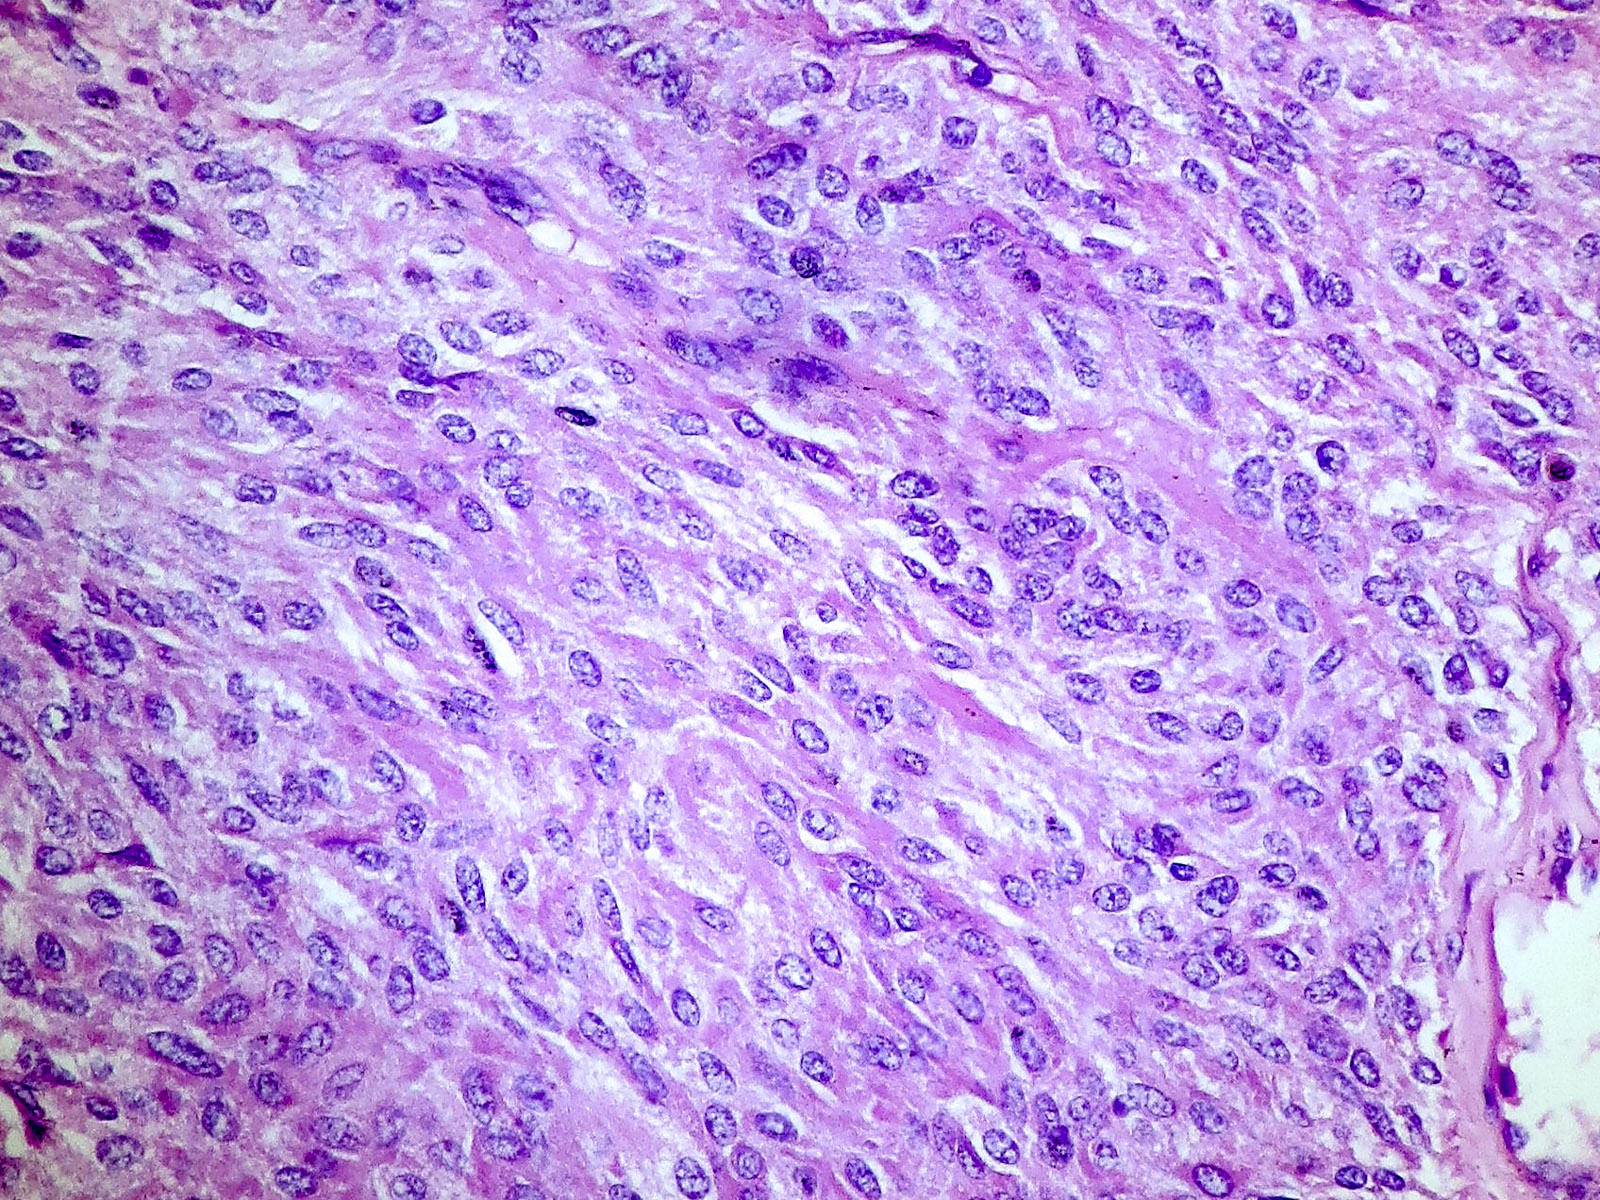

Microscopic (histologic) description

- Wide variety of morphology, can mimic any other thyroid malignancy

- Round, plasmacytoid, polygonal or spindle cells in nests, cords or follicles; often mixtures of these cells

- Round nuclei with finely stippled to coarsely clumped chromatin and indistinct nucleoli, occasional nuclear pseudoinclusion

- Eosinophilic to amphophilic granular cytoplasm due to secretory granules

- Generally low mitotic figures

Microscopic (histologic) images

Contributed by Shuanzeng Wei, M.D., Ph.D., Joseph Christopher Castillo, M.D. and Mark R. Wick, M.D.